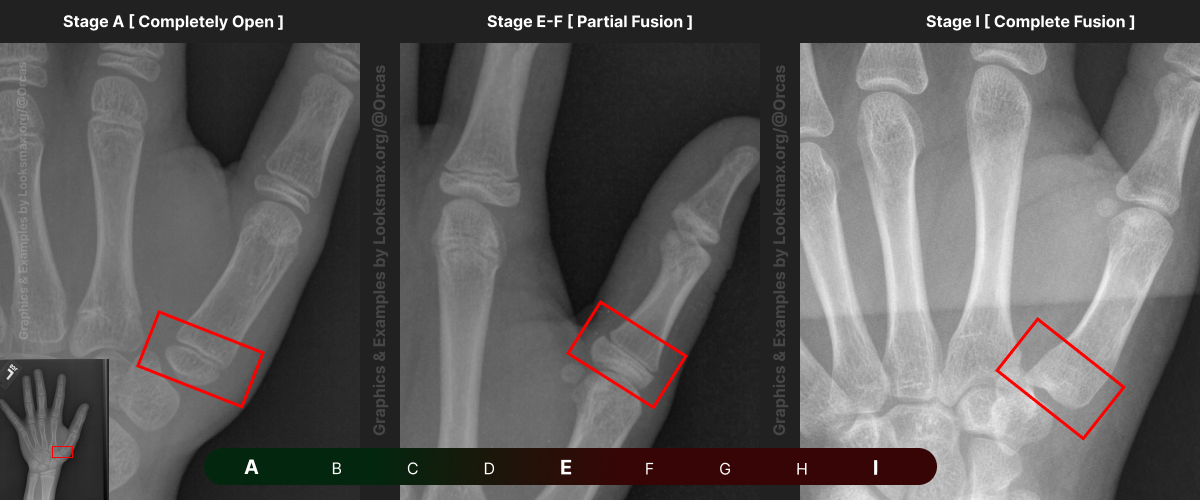

I added references for stages A (Completely unfused), E-F (Partial fusion, basically late stages of puberty), and I (Complete Fusion)

You will have to eyeball this now using your own xrays, I’ve given three examples and some wiggle-room for letters using a reference bar (green-red) below the image, write down your estimated guesses in a text file until you finish all 13 bones.

Don’t doubt yourself, eyeballing isn’t perfect but it still works well, just choose & continue.

Ex.

“My Radius looks more fused than the image from E-F, but its not as fused as I, it’s closer to the 2nd picture though, so I’ll rate it G” And continue

Bonetype: 3rd Middle Phalanx

Check & use the chart below to figure out where you are. Then write your result on a piece of paper or a text file.

Bonetype: 5th Middle Phalanx